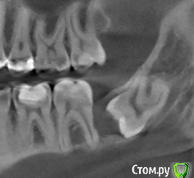

Подскажите пожалуйста, как правильно поступить с моими 8-ками?

Их, действительно, надо срочно удалять? Мне 28 лет. Какова вероятность, что они меня вообще не побеспокоют?

Какие существуют риски их удалять и какие риски их не удалять ?

post-51158-0-42449500-1490961204_thumb.png